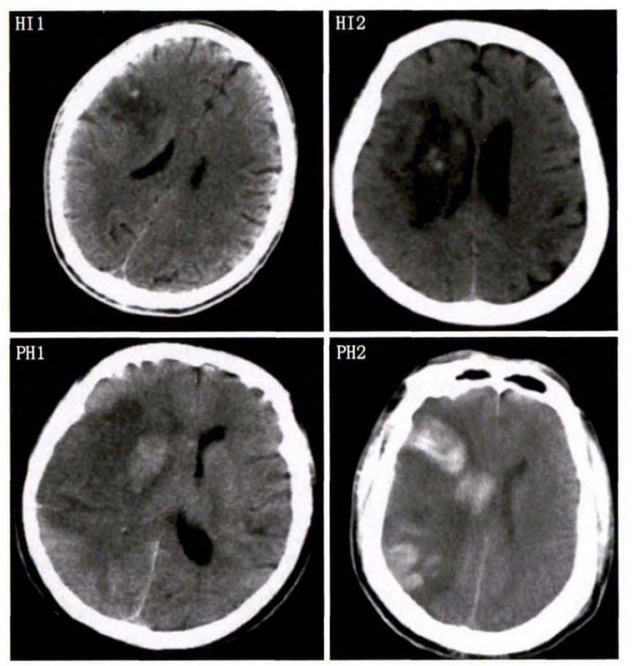

中、老年病患,有動脈粥樣硬化及高血壓病等腦卒中的危險因素,發(fā)病結合神經系統(tǒng)癥狀和體征,應當考慮急性腦梗死的可能。再經腦CT/MRI發(fā)現梗死灶,或排除腦出血、炎癥性疾病等,診斷即可確定。腦梗死有時頗似小量腦出血的臨床表現。腦栓塞在任何年齡都可以有發(fā)病的風險,可以在幾秒到幾分鐘達到頂峰。會有偏癱不能說話等局部神經功能損壞。栓子來源很種,可能是冠心病、心肌梗塞、心內膜炎等。合并心房纖顫,結合其他臟器官的支持診斷,CT跟磁共振都可以檢查確定栓塞位置數量還有是不是有伴發(fā)出血等問題??梢詭椭\斷。

中老年有高血壓糖尿病發(fā)病病史,起病神經功能缺損癥狀,臨床表現為腔隙綜合征,即可初步診斷本病。如果CT或磁共振證實有與神經功能缺失一致的腦部腔隙病灶, 符合大腦半球或腦干深部的小穿通動脈病變,即可明確診斷。少數患者隱匿起病,無明顯臨床癥狀,在影像學檢查時發(fā)現。